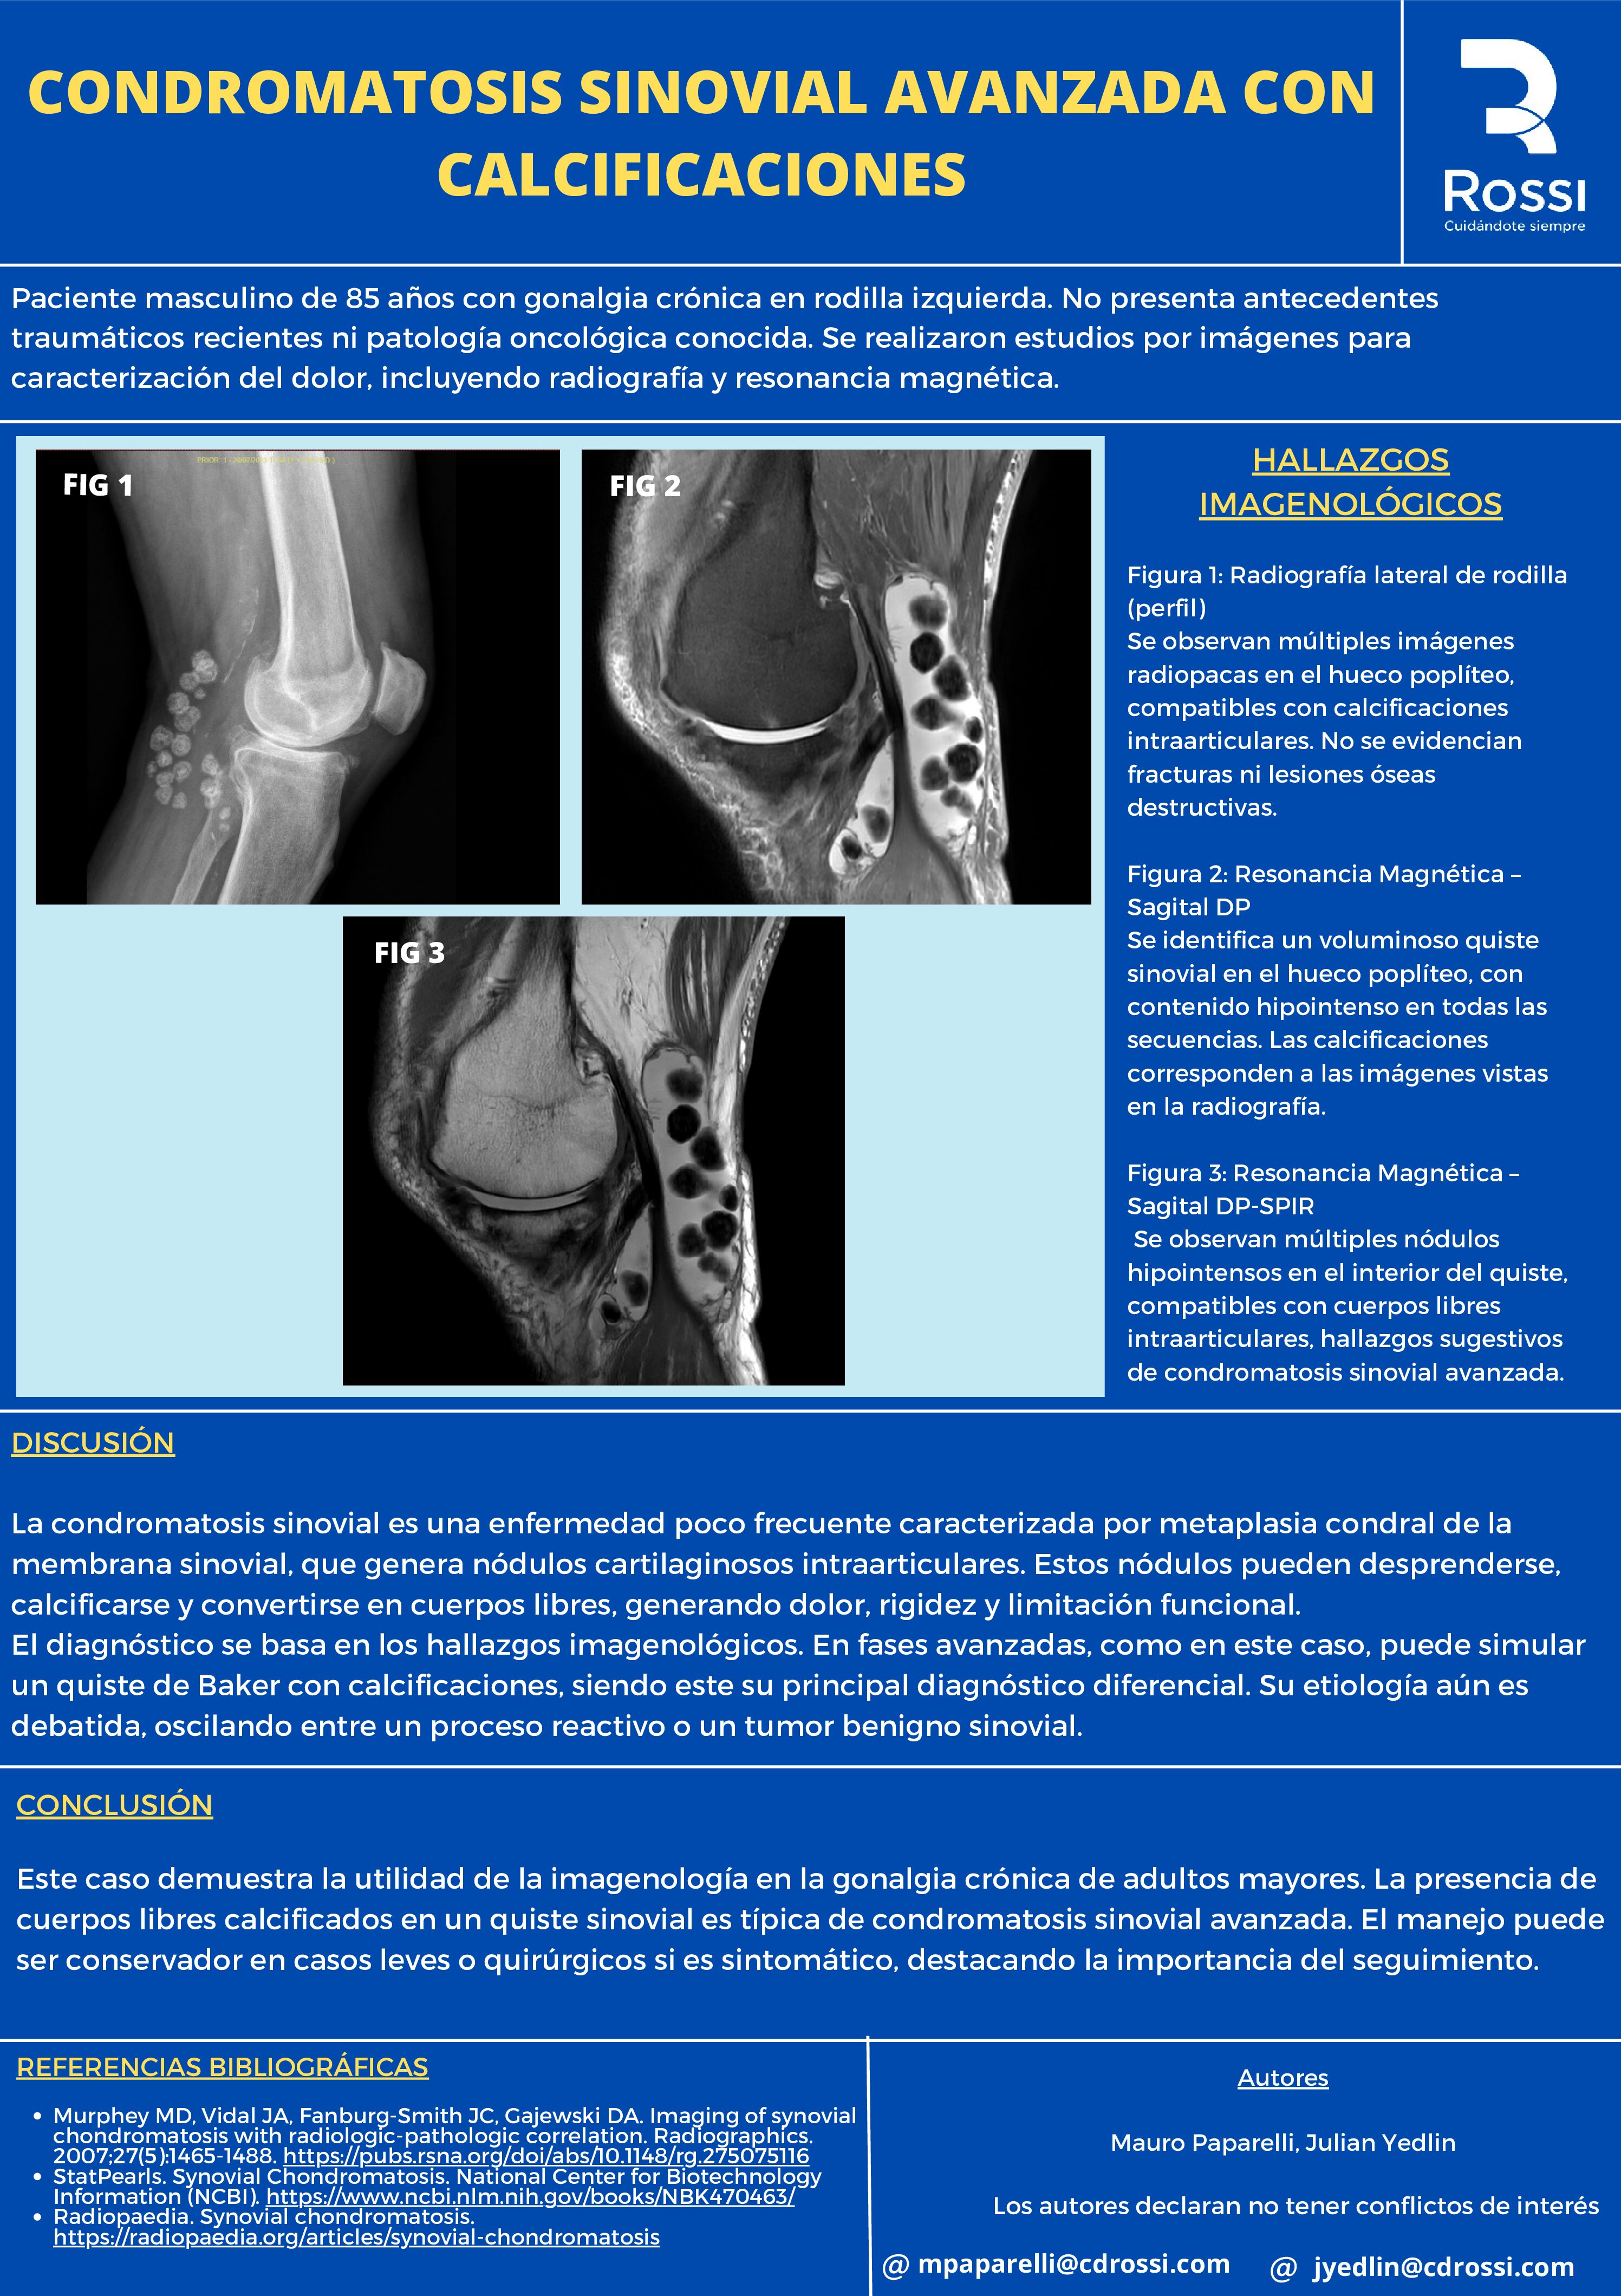

CONDROMATOSIS SINOVIAL AVANZADA CON CALCIFICACIONES